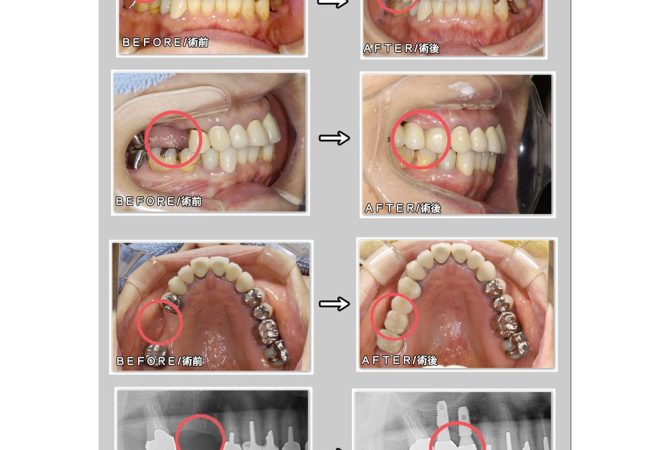

インプラントの症例 GBR法/骨補填材使用